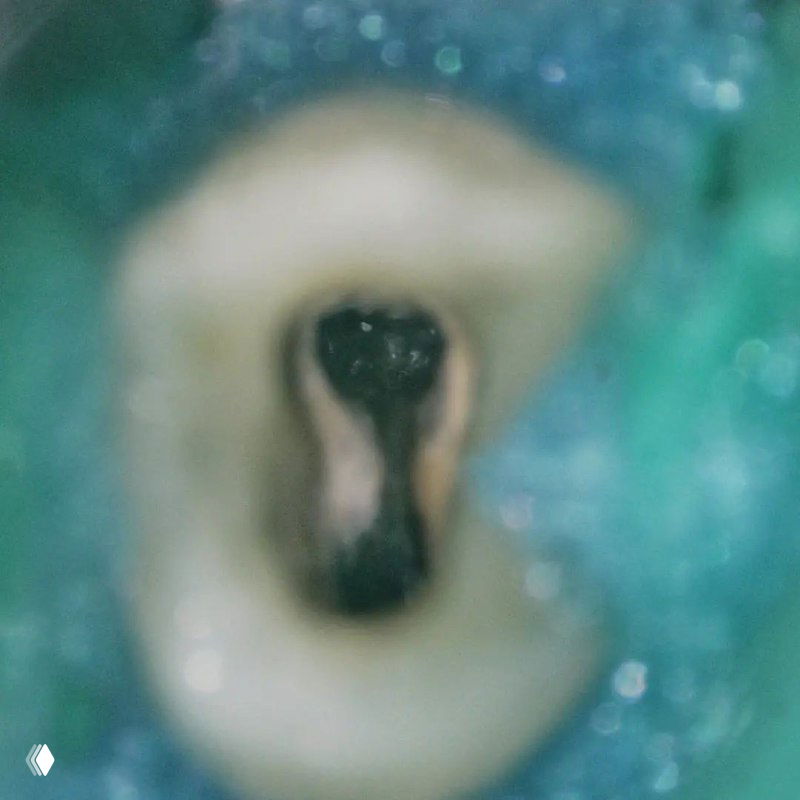

На что обратить внимание:

- классическую овальную полость доступа нужно немного расширить в области щёчных каналов в мезио-дистальном направлении

- проводить аккуратное расширение щёчных каналов, так как в области данных корней очень мало дентина (в моём случае расширение 25.04)